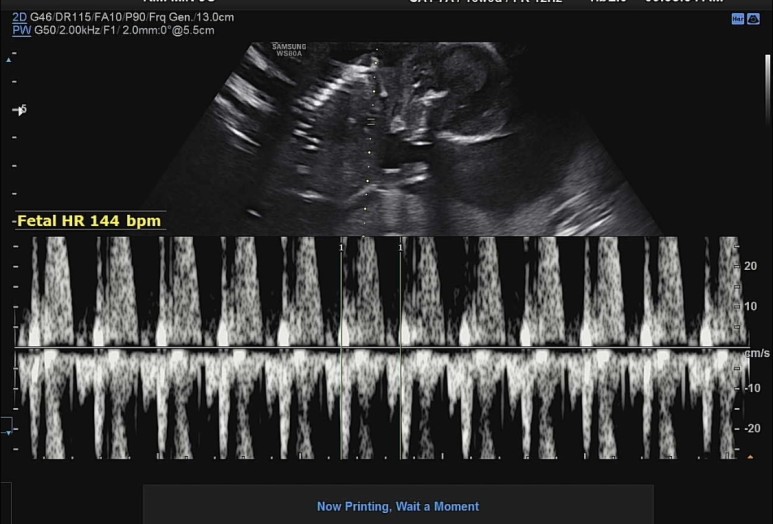

일단 심장소리. 쿠궁쿠궁.

꿀잠이 오늘의 바이탈 144bpm!